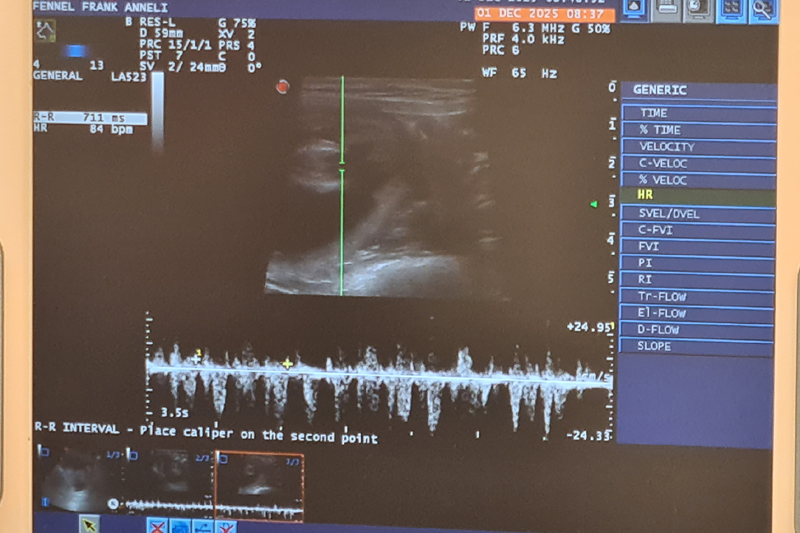

Inga valpar....

Fennel är tyvärr inte dräktig. Vi har tyvärr haft otur igen med fryst sperma. Det är så trist för det finns så många fantastiska hanar där ute i världen

som jag så gärna vill ha i min avel. Men vi ger inte upp så lätt!